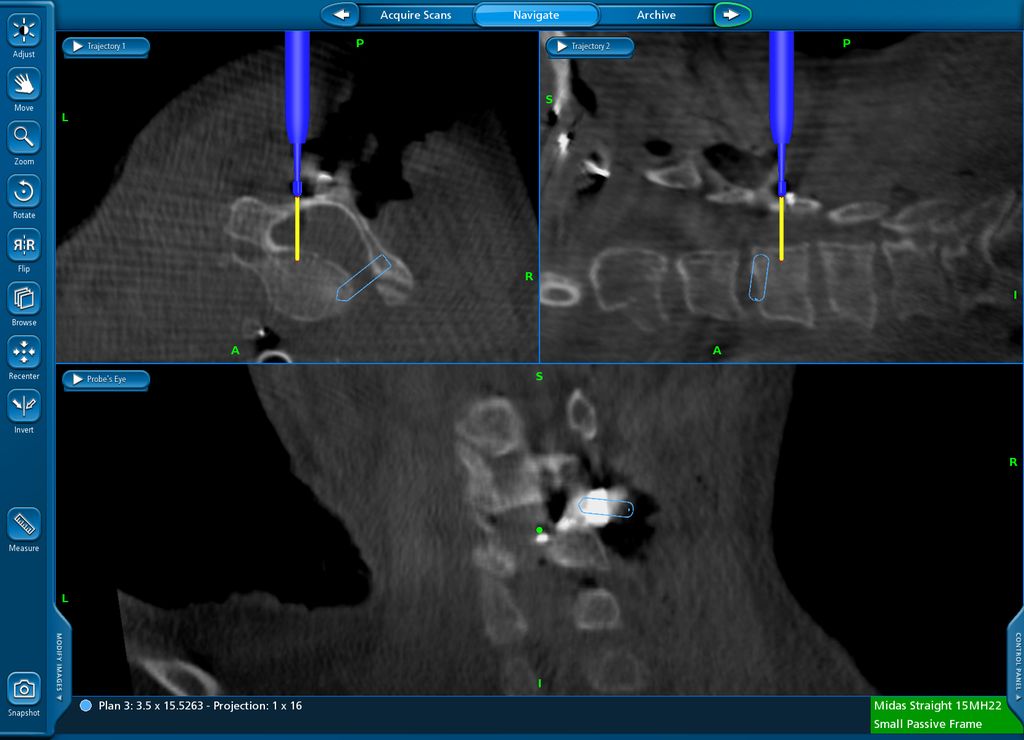

Beispiel für die Implantation zervikaler Pedikelschrauben. In diesem Fall kam es bei einem 61-jährigen Patienten 10 Jahre nach anteriorer zervikaler Diskektomie und Fusion (ACDF) C4/5 und ventraler Verplattung C4–6 zu einer Ankylosierung auch von C6/7. Nach Sturz kam es zu einer Fraktur bei C6/7 mit begleitender Bogenfraktur und auch Beteiligung der dorsalen Ligamenta (Abb. 1 und 2). Klinisch bestanden ausgeprägte Nackenschmerzen und kein neurologisches Defizit. Es wurde die Indikation der dorsalen Verschraubung von C4 auf Th1 gestellt. Intraoperativ wurde routinemäßig zusätzlich eine kleine Referenzschraube in einer Lamina – entfernt von der Dornfortsatz-Referenzklemme für die Navigation – gesetzt. Mit dieser konnte intraoperativ die Genauigkeit der Navigation exakt überprüft werden (Abb. 4 und 5). Mittels navigierter High-Speed-Fräse wurden die Schraubenkanäle vorgebohrt (Abb. 6), im Anschluss wurde der Bohrkanal ausgetastet und die Schrauben wurden implantiert. Abbildung 7 zeigt eine Röntgenkontrolle 3 Monate postoperativ.

Abb. 4: Screenshot der Navigationssoftware intraoperativ (Stealth Station S7). Es erfolgt die intraoperative Verifizierung der Navigationsgenauigkeit mittels kleiner Schraube in der Lamina, positioniert idealerweise entfernt von der Dornfortsatz-Referenzklemme. Die navigierte Fräse wird im Situs exakt auf die Schraubenmitte gerichtet, und die Navigation bestätigt die Genauigkeit | |